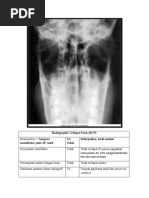

Examination = Manus YaatauTidak

Oblique

Gambaran anatomi dalam Ya - Tampakgambaran Carpal, Metacarpal, Phalangdalamposisi Oblique

radiograf? - Tampak Caput Metacarpal 3-5 sedikit overlap,

- MCP dan Interphalangeal membuka

- Soft tissue tampak

Apakah gambaran anatomi Ya SeluruhbagianManustampak. Terlihatdari distal Phalang 1-5 sampaiP

tampak sesuai dengan

proyeksi ini?